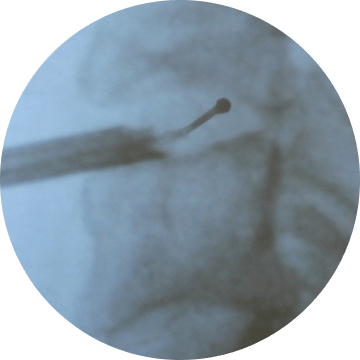

Радиочастотная Disc-FX дискэктомия —

по-настоящему малоинвазивная методика в лечении протрузии межпозвонкового диска

Чрескожный заднелатеральный

доступ через канюлю диаметром

3,0 миллиметра

Стандартная механическая

нуклеотомия с использованием

миниатюрных кусачек

Управляемый, гнущийся электрод — точная локализация радиочастотного воздействия на пульпозное ядро и фиброзное кольцо

Управляемый, гнущийся электрод позволяет точно локализовать радиочастотное воздействия на пульпозное ядро и фиброзное кольцо

доступ через канюлю диаметром 3,0 мм

Под контролем флюороскопии, эндоскопия опционально

Контроль посредством флюороскопии, эндоскопия опционально